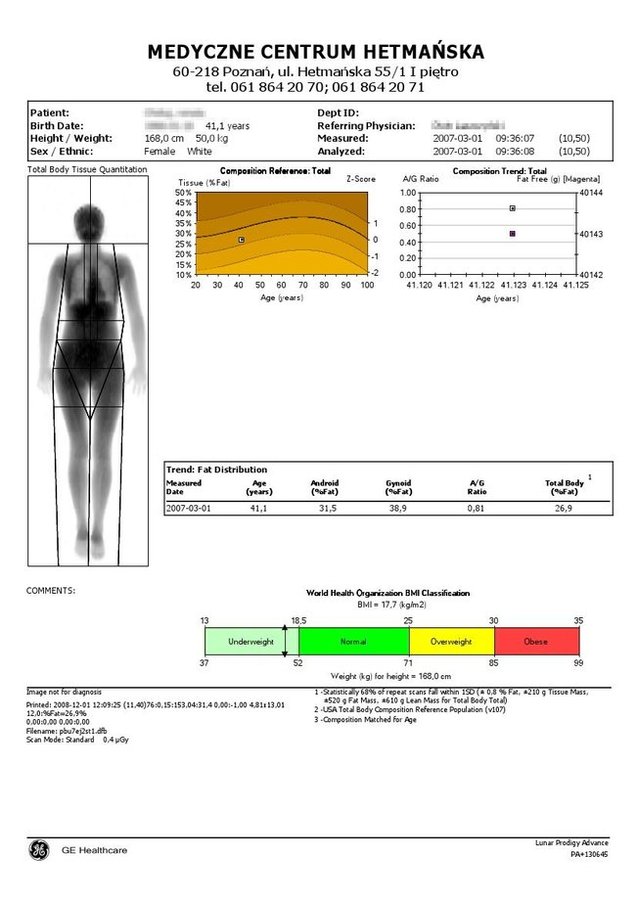

• W badaniu Total Body ocenie poddana zostaje masa tkanki kostnej całego szkieletu poprzez wyznaczenie gęstości w g/cm². Następnie dzięki specjalnemu oprogramowaniu aparat Lunar – Prodigy porównuje wynik do wartości szczytowych dla danej płci lub kontrolnej grupy rówieśniczej.

• Podczas badania densytometrycznego całego kośćca analizie poddany zostaje także skład ciała z wyznaczeniem masy tkanki tłuszczowej (Fat mass) oraz jej procentowego udziału względem masy ciała (% Fat), a także rozkładu percentylowego względem populacji referencyjnej.

Ramię densytometru przesuwa się nad pacjentem skanując cały kościec i skład ciała. Na ekranie komputera pojawia się skanowany obraz, dokonywany jest pomiar gęstości mineralnej kości w g/cm2, pomiar zawartości tłuszczu i tkanki mięśniowej w gramach.

Pacjent otrzymuje wynik przeprowadzonego badania w formie wykresu i tabeli.